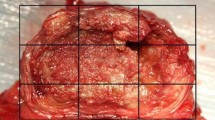

Histology

All specimens were fixed in phosphate-buffered formalin solution for a minimum of 48 h and decalcified in 10% formic acid–phosphate-buffered formalin solution for routine paraffin histology. Each specimen was sectioned into four blocks in the sagittal plane, so that the cranial endplate, IVD and caudal endplate were localised for each disc space. Each IVD was macroscopically assessed, paying attention to gross appearance, tissue architecture, and presence of fibrous tissue. The blocks (~ 3 mm in thickness) were embedded in paraffin and sectioned (5 microns) using a Leica Microtome (Leica Microsystems Pty Ltd, North Ryde, Australia). A minimum of three sections were cut from each paraffin block and stained with hematoxylin and eosin (H&E). Stained sections were examined in a blinded fashion (to treatment groups and timepoints) using an Olympus light microscope (Olympus, Japan) with a DP72 high-resolution video camera (Olympus, Japan). Eighteen discs from the six control rabbits used for mechanical testing were also evaluated. The stained sections were graded by a single observer blinded to rabbit ID, group and timepoint, using the recently established standardised histopathology scoring system of rabbit IVD degeneration (Fig. 3) [30]. Briefly, a three-category grading scheme (grade 0–2) across seven evaluated categories was used: NP morphology (shape and area), NP matrix condensation, NP cellularity, AF/NP border appearance, AF morphology, and endplate (EP) sclerosis/thickening. The total histological score (0–14) was calculated by summing grades across all categories, with greater scores indicating greater degeneration. Paraffin blocks from animals in each group and timepoint (n = 1 per treatment group per timepoint and n = 1 adjacent control disc) were selected for additional staining with Safranin-O (SO) and Picrosirius Red (PR) for qualitative analysis.

Histological IVDD grading system used in this study, as described by Gullbrand et al. (2021) [30] for preclinical in vivo rabbit studies

Macroscopic assessment of intervertebral discs

The condition of NP and AF tissue was assessed via macroscopic observation of freshly dissected IVD samples. For the non-operated adjacent and control IVDs, transparent, white, hydrated, fresh NP tissue was visible in the centre of the disc, almost oozing from within the disc space (Fig. 7A). The normal concentric lamellae structure of the AF was evident, clearly demarcating the boundary of the disc space and encapsulating the NP. For all fenestrated IVDs, the disc space was visibly collapsed with the majority of NP removed (Fig. 7B). The remaining tissue was degenerate, the AF structure was distorted, and the overall structure of the IVD was abnormal. There was significant fibrous tissue formation on the left lateral aspect of the annulus/intervertebral space (Fig. 7B, C). There were palpable osseous thickening/proliferations at the lateral extremity of the transverse processes on the left-hand side.

Stereozoom microscopic appearance in the sagittal plane (1 × objective) of L3/4 IVDs for the following conditions: age-matched non-operated control (A), 6 weeks (B) and 12 weeks (C) post-fenestration. For the fenestrated IVDs (B, C), note the gross distortion of the IVD architecture, lack of differentiation of the NP from the AF and fibrous tissue formation on the ventral aspect of the disc space (greatest at 12 weeks post-fenestration). Abbreviations: AF Annulus Fibrosus, EP Endplate, FT Fibrous Tissue, NP Nucleus Pulposus, SC Spinal Cord, VB Vertebral Body, VLL Ventral Longitudinal Ligament

Histology

Qualitatively, all fenestrated IVDs showed a combination of defects involving the AF and NP without signs of extrusion, along with degenerative and inflammatory changes. Fenestrated IVDs showed alterations in NP and AF morphology, blood vessel ingrowth, influx of mixed inflammatory cells and adherence of fibrous tissue, predominately on the left ventrolateral aspect of the disc space (Fig. 8B, C, E). Fenestrated IVDs scored at high severity for all evaluated categories, reflecting the structural changes of the AF and the NP, with distortion of the AF/NP boundary and the AF lamellar structure on the left ventral and lateral aspects.

Haematoxylin and eosin (H&E) stained light-microscopic histopathological images of L3/4 IVDs for the following conditions: age-matched non-operated control (A, D), and 12 weeks (B, C, E) post-fenestration. For the fenestrated IVDs, note the obliteration of endplate cartilage on the cranial endplate at low magnification (B) and under high magnification, amorphous bone formation with inter-weaving fibrous tissue and mixed inflammatory infiltrates on the ventral aspect of the disc space at 12 weeks post-fenestration (C). The control sample shows highly aligned AF lamellae (D) compared to disorganised lamellae fibres from a fenestrated IVD 6 weeks postoperative (E). Abbreviations: B Bone, AF Annulus Fibrosus, CCB Cancellous Bone, EP Endplate, FT Fibrous Tissue, NP Nucleus Pulposus

There was evidence of endplate sclerosis at all operated IVDs. Blood vessel ingrowth was observed within the AF and into the NP to a lesser extent. There were increased populations of mixed mono and polymorphonuclear inflammatory cells (macrophages, lymphocytes, plasma cells and neutrophils), with interspersed moderately well organised fibrous connective tissue (fibroblasts), on the left lateral annulus, consistent with AF and NP injury and secondary biological response (Fig. 8B, C, E). There was also amorphous bone formation at this location, consistent with osteophytosis (Fig. 8C). In the adjacent non-operated and age-matched control groups, the NP tissue was well organised, resembling an oval shape and a clear boundary to AF (Fig. 8A). The NP matrix had a gelatinous appearance, with reduced cell density. Cartilaginous endplates were thin with many adjacent vascular channels. There was normal cell density within the NP.

Quantitative grading, where a higher score indicates a more degenerative disc, supported the above histological observations. The injured IVDs had statistically significant higher total histological scores than non-operated adjacent and age- matched control IVDs for both single and multiple groups at 6 and 12 weeks (P < 0.001) (Table 4). No significant difference was detected between non-operated adjacent and age-matched control IVDD scores in either group or timepoint. There was no significant effect of group or timepoint on histological scores. For adjacent non-operated control discs stained with SO, the nucleus stained intensively for proteoglycans. The endplates had a regular homogenous thickness and cartilage structure with chondrocytes embedded in a rich proteoglycan matrix, demonstrated by intense red staining (Fig. 9A, B). For fenestrated discs, there was marked reduction in red staining suggestive of reduced proteoglycan content albeit in a more collapsed disc space relative to the intact (Fig. 9C). Picrosirius staining demonstrated the normal concentric lamellar layers of collagen on the ventral aspect of the AF (Fig. 10A). In comparison, the disc space of fenestrated samples was collapsed, with disruption and loss of continuity of the normally well-arranged and aligned lamellar fibres suggestive of degeneration.